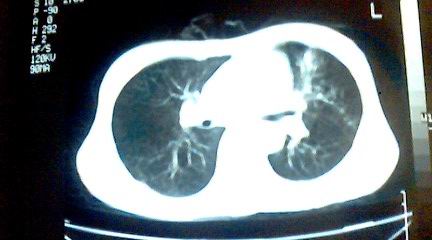

标题: CT25218:请教!胸部CT,胸8椎体骨质破坏,伴周围软组织肿。

患者,女41岁,肢体乏力。

两肺上叶继发性肺结核;胸椎结核并椎旁寒性脓肿形成。

两肺上叶继发性肺结核;胸椎结核并椎旁寒性脓肿形成